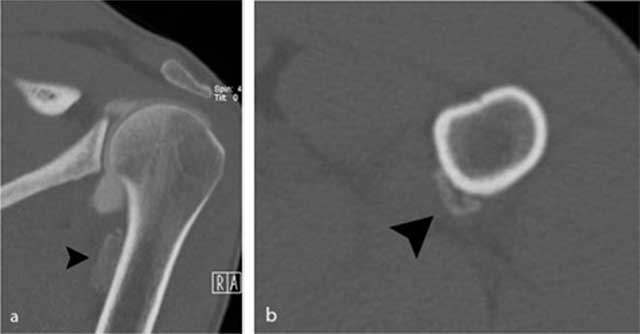

Figure 3

Additional CT images of the proximal humerus. a) Oblique coronal reformatted images and b) axial reformatted images reveal the presence of an extra-articular calcification (black arrowhead) near the insertion of the teres major tendon.